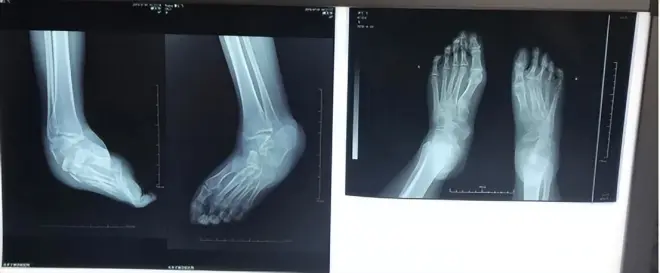

通过胡霞医生的精心治疗,大大改善了足踝畸形,实现了独立行走的梦想。今年夏天来复查,X光显示她右脚的形态明显改善,变得更加清晰明了,骨块完整无损,没有进行任何切割或内固定手术,关节也恢复了原本的位置。